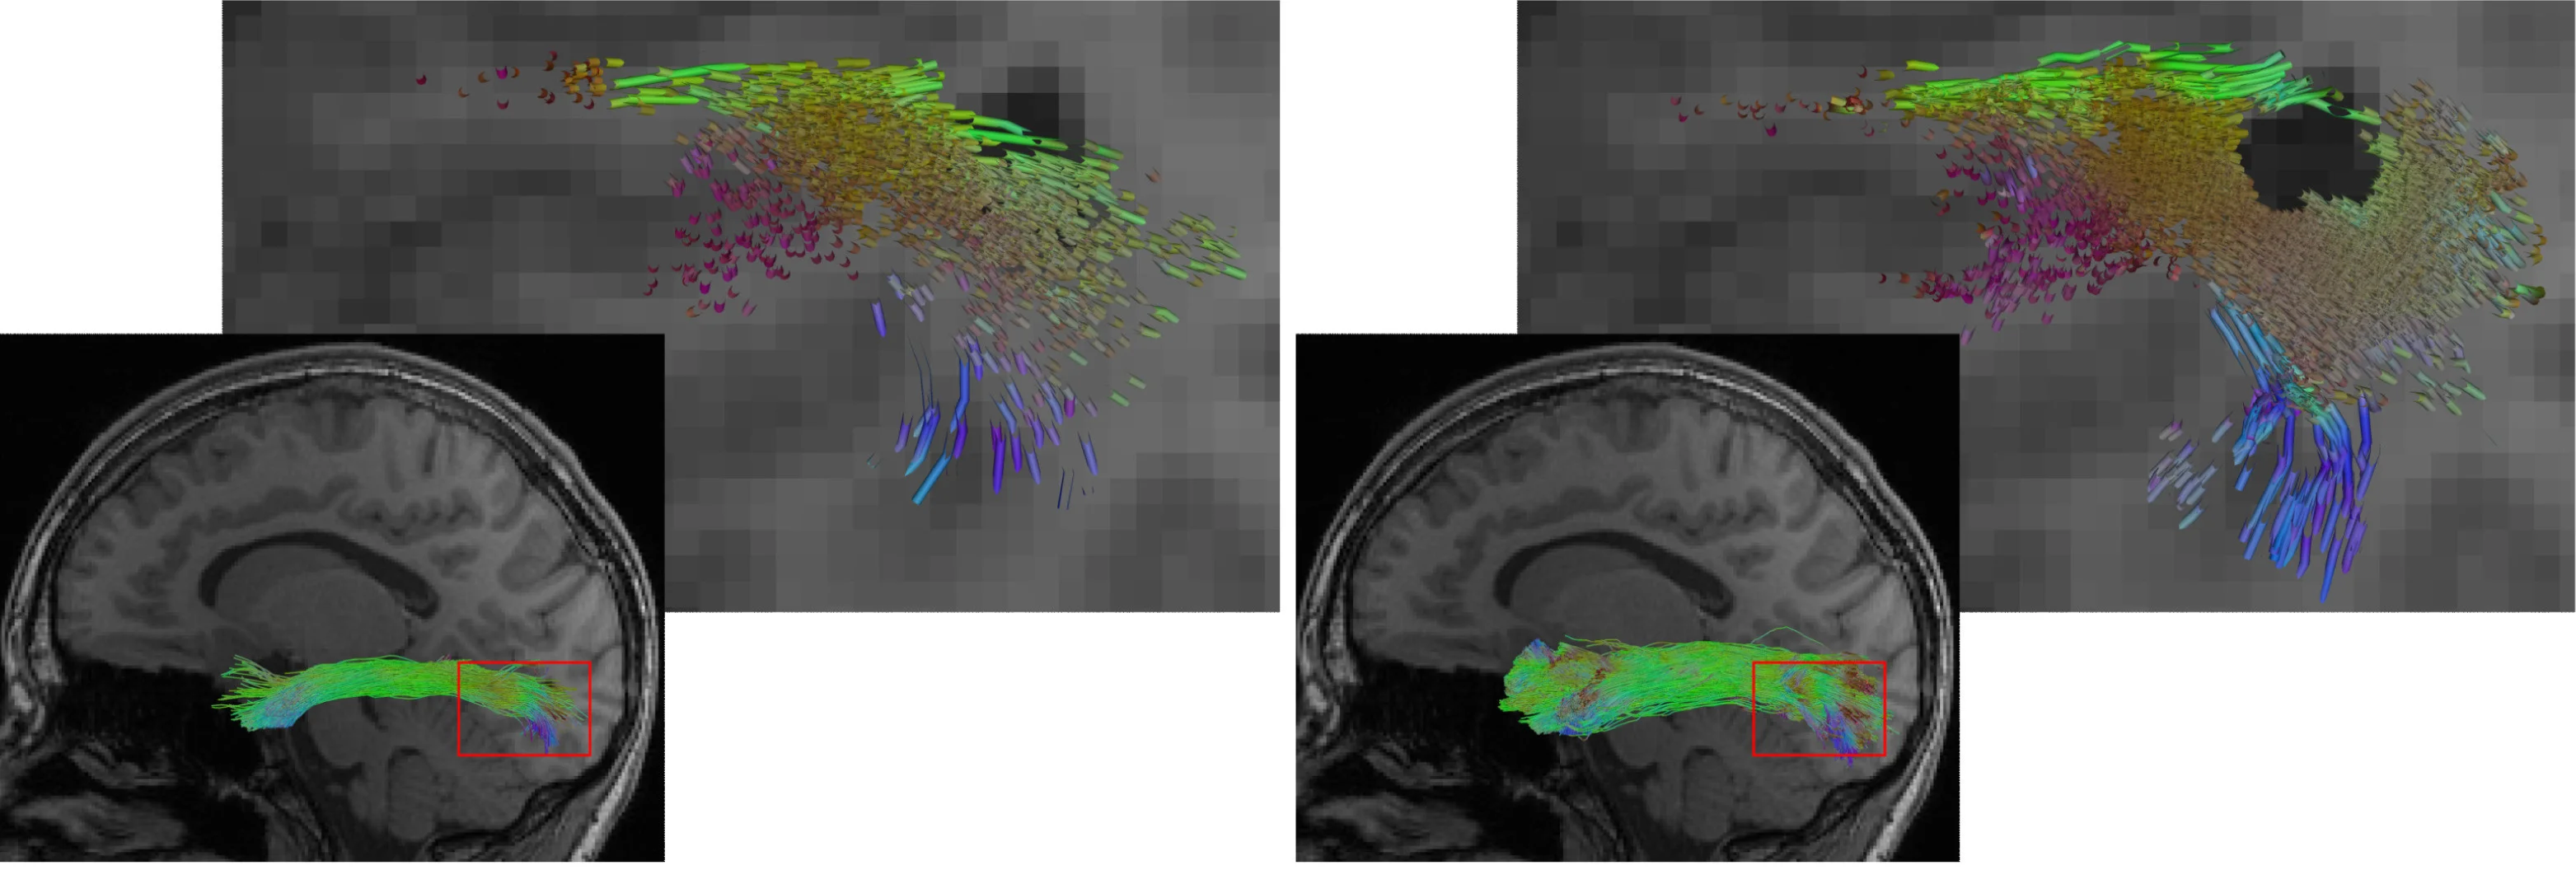

Die Abbildung zeigt eine Rekonstruktion des Fasciculus longitudinalis inferior (ein Fasertrakt des Gehirns), links mit einem herkömmlichen KI-Verfahren, rechts mit dem neuen Hybridansatz. Der Hybridansatz ermöglicht eine vollständigere Rekonstruktion. Zugleich spart er Läsionen wie die dunkle Region in der Detailansicht präziser aus.